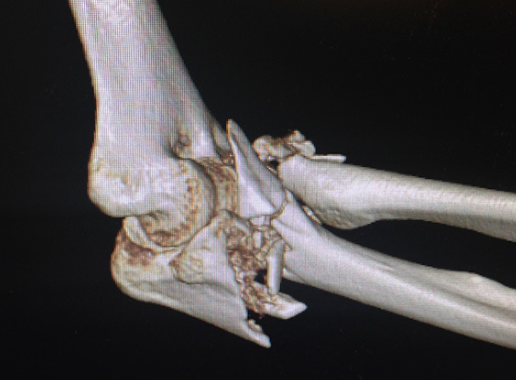

골절:Fractures

설명: 골절은 팔꿈치를 구성하는 뼈 중 하나 이상이 부러지는 것을 의미합니다. 이러한 부상은 주로 낙상이나 직접적인 충격으로 인해 발생합니다.

증상: 극심한 통증, 부종, 변형된 팔꿈치의 모양, 그리고 사용할 수 없는 팔의 기능입니다.

- X-ray (X선): 뼈의 상태를 평가하여 골절이나 관절염 같은 문제를 진단할 수 있습니다.